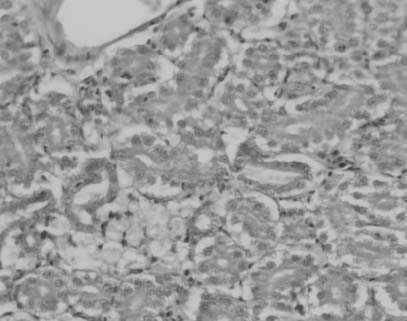

Figura 2. Imágenes histológicas características de cada grupo experimental: a) grupo A; b y c) grupo B; d) grupo C; e) grupo D; f) grupo E. CR: corpúsculo renal; fi: focos inflamatorios; flechas: grasa; barra en a, b, d, e, f: 30 mm; barra en c: 50 mm.

En el grupo A, grupo control o de individuos sanos, no se observaron depósitos de grasa, focos inflamatorios ni daño glomerular. Tampoco se observó fibrosis (fig. 2a).

En el grupo B, grupo control con dieta aterogénica, destacaban numerosas acumulaciones de grasa, que en muchas ocasiones ocupaban prácticamente todo el citoplasma en varias células contiguas, formando grandes acumulaciones grasas. En algunos cortes se observaban focos inflamatorios difusos rodeando las acumulaciones grasas. El mesangio de los glomérulos aparecía habitualmente denso y, en ocasiones, algunos casos obliterando la luz, características indicativas de daño glomerular (fig. 2b).

En el grupo C, grupo de regresión con dieta normal sin intervención con atorvastatina, se observaron numerosos depósitos grasos, aunque de menor tamaño y en menor cantidad. No eran destacables los focos inflamatorios. Los glomérulos presentaban un aumento del mesangio, aunque en menor cantidad que el grupo B. No se observaba fibrosis (fig. 2c).

En el grupo D, grupo de regresión con dieta normal e intervención administrando atorvastatina, las acumulaciones grasas prácticamente eran inexistentes y se asemejaban a las características del grupo control A. No se observaban focos inflamatorios. No destacaba daño glomerular ni fibrosis (fig. 2d).

En el grupo E, grupo de progresión con dieta aterogénica e intervención con atorvastatina, se describieron también grandes acumulaciones grasas y pequeños depósitos intracelulares aislados. Se observaron pequeños focos inflamatorios, daño glomerular moderado y no destacó fibrosis (fig. 2e).